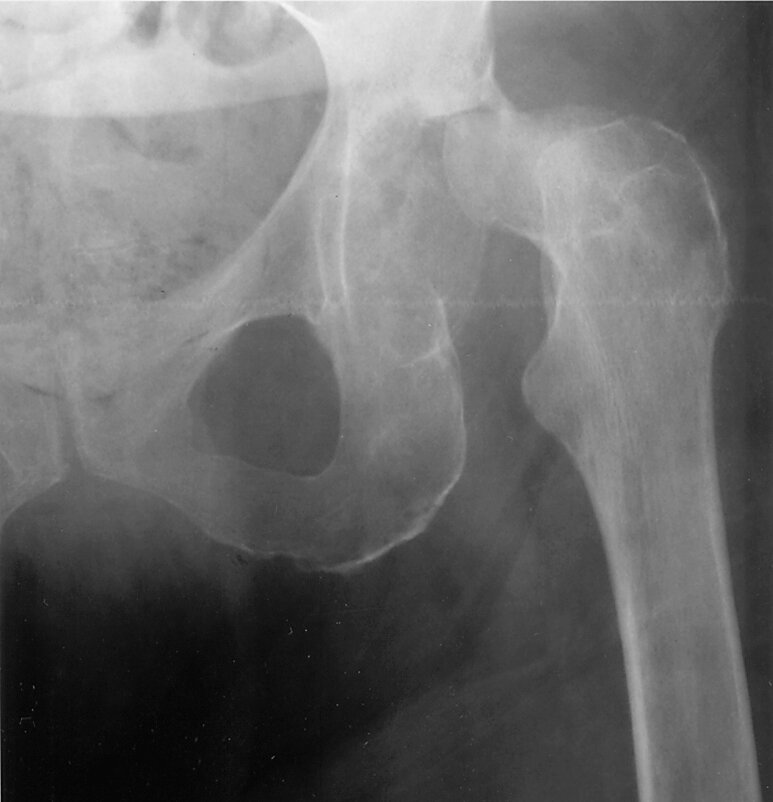

A 45-year-old man with a history of rheumatoid arthritis is evaluated for fever and left hip pain that has become progressively severe over the past 6 weeks.

A radiograph of the hip is shown.

Which of the following is the most likely diagnosis?

A) Avascular necrosis

B) Septic Arthritis

C) Gout

D) Calcium pyrophosphate deposition disease

Septic Arthritis

-cortical destruction on acetabular and femoral sides of the joint

- Radiographs of the infected joint may show periarticular osteopenia but are usually normal at presentation, but should be obtained to identify associated osteomyelitis or concurrent arthritis.